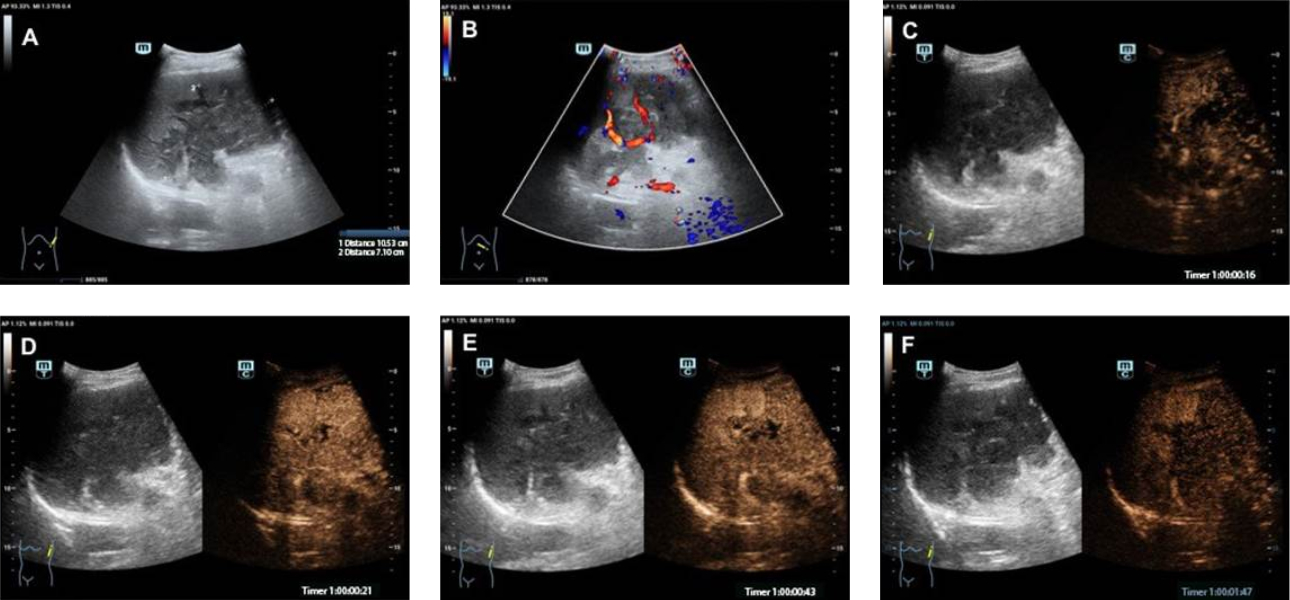

형상1: B-모드 초음파 검사에서는 비장실질(splenic parenchyma)로 돌출되고 비장문(splenic hilum)을 침범한 불균질형 종괴(heterogeneous mass)가 췌장 꼬리(pancreatic tail)부분에서 보이는 커진 불균질형 췌장(heterogeneous pancreas)이 확인되었습니다. (Fig 1 A). 컬러도플러 영상(Color Doppler imaging ; CDI) 로 해당 종괴(mass)내 혈류가 관찰되었고 (Fig 1 B). 췌장 종괴(pancreatic mass)에 진행된 CEUS 검사는 동맥기(arterial phase)에서 불균질형 과도증가(heterogeneous hyperenchancement)를 지연기(delayed phase)에는 빠른 퇴색(rapid fading)및 체와 같은(sieve-like) 변화를 보여주고 있습니다. (Fig 1 C-F)